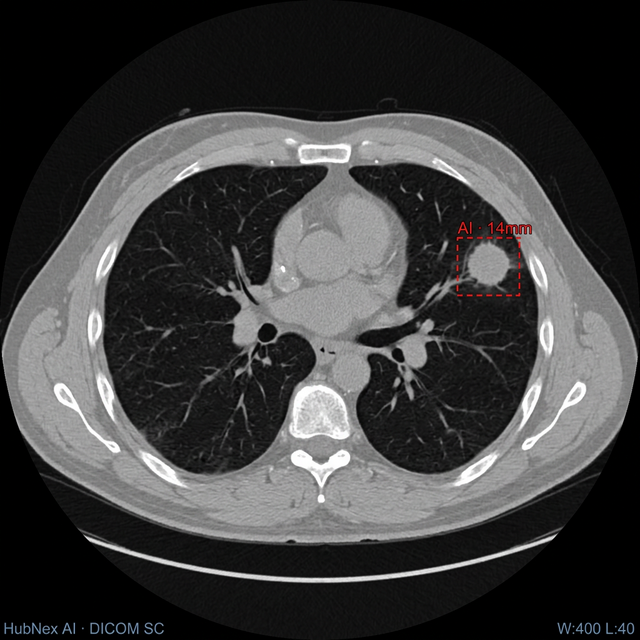

AI annotations, bounding boxes, and measurements are baked directly into the DICOM — rendered as Secondary Captures readable in any viewer. Clinical history and labs are pre-populated into your dictation software.